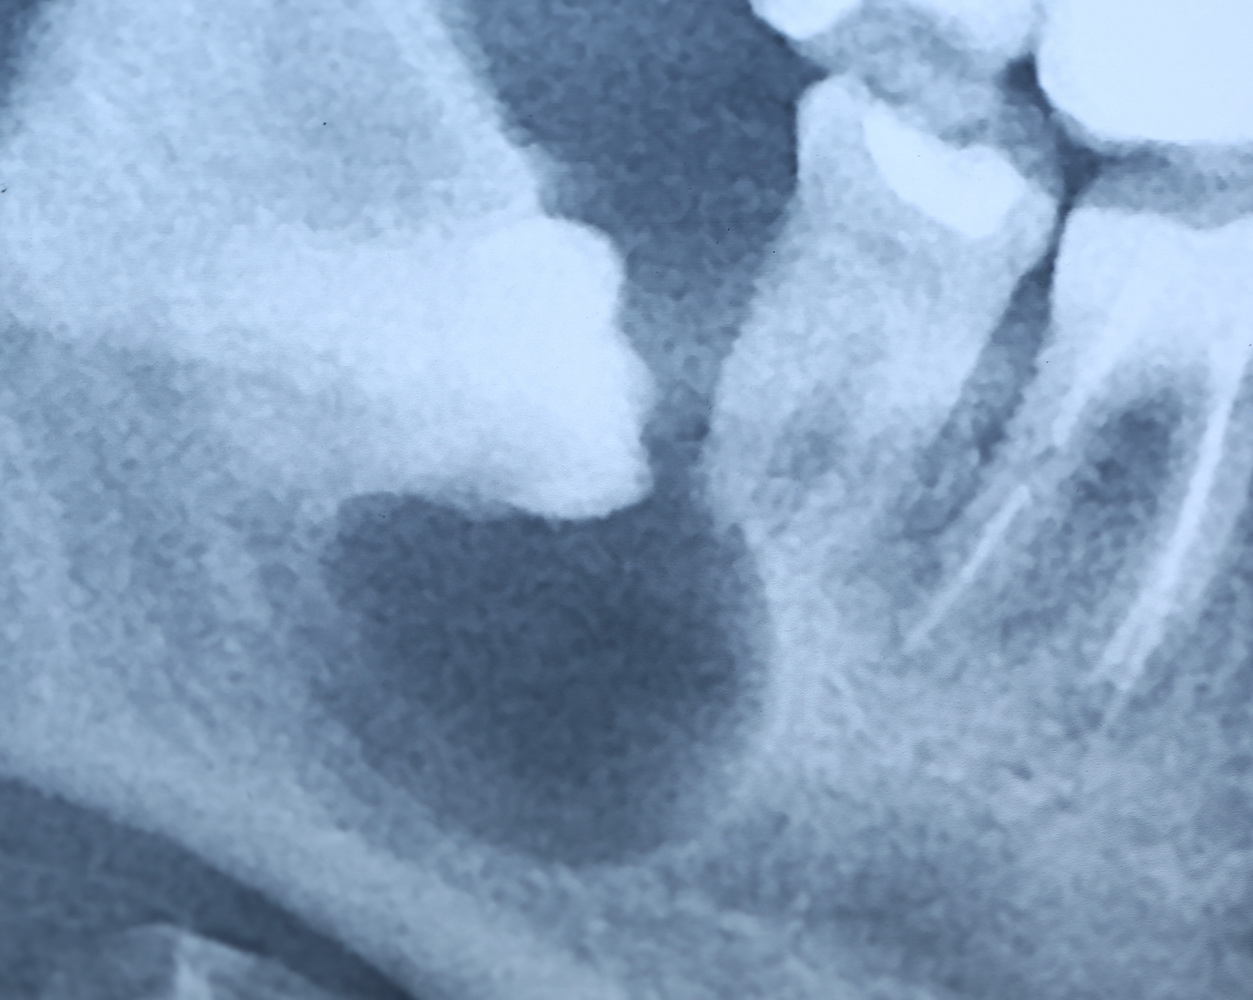

Вот разбор снимка:

Давайте еще раз посмотрим на снимок:

Что мы на нем видим? Ну да, есть два лишних зуба.

К сожалению, мы не можем по ортопантомограмме…

- … достоверно определить положение зубов. Ортопантомограмма искажает.

- …определить их отношение к нижнечелюстному каналу и соседним зубам. Они находятся ближе к щеке или языку? Нижнечелюстной канал проходит за, между или перед ними? Мы должны ОБЯЗАТЕЛЬНО знать ответы на эти вопросы.

- … самое главное — спланировать операцию в целом и схему операционного доступа, в частности! Это важно? Еще как!

Что, собственно, мы и делаем:

По-моему, на скриншоте всё понятно. Зубы, которые нужно удалить нафиг, обозначены белой стрелкой и словосочетанием «удалить нафиг!«. Темным пунктиром обозначены контуры зубов. Черная точка — просвет нижнечелюстного канала. Снизу слева я попытался наглядно показать схему взаимного расположения и отношения сверхкомплектных зубов к нижнечелюстному каналу. Ну и, внимательно изучив КТ, я принял решение, что операционный доступ нужно делать с язычной стороны.